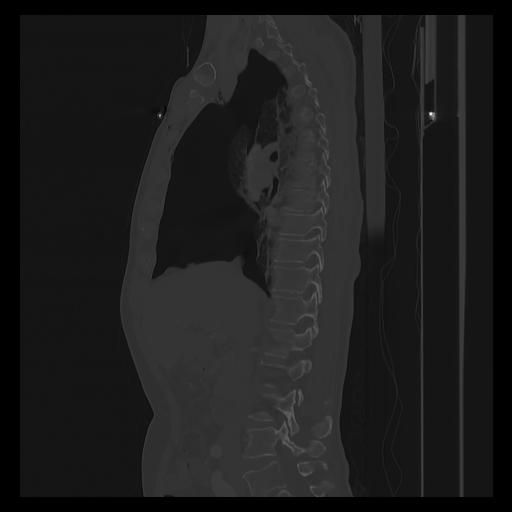

33 PULMON,CE,Sagittal,3.000,PULMON,Sagittal,